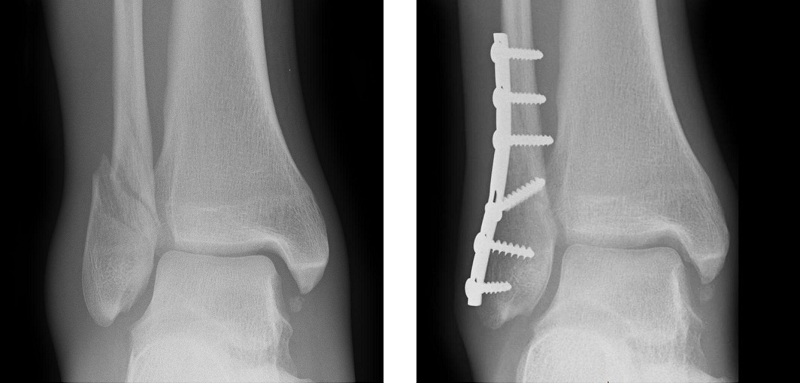

Separting regions of x-ray images (e.g., teeth images)